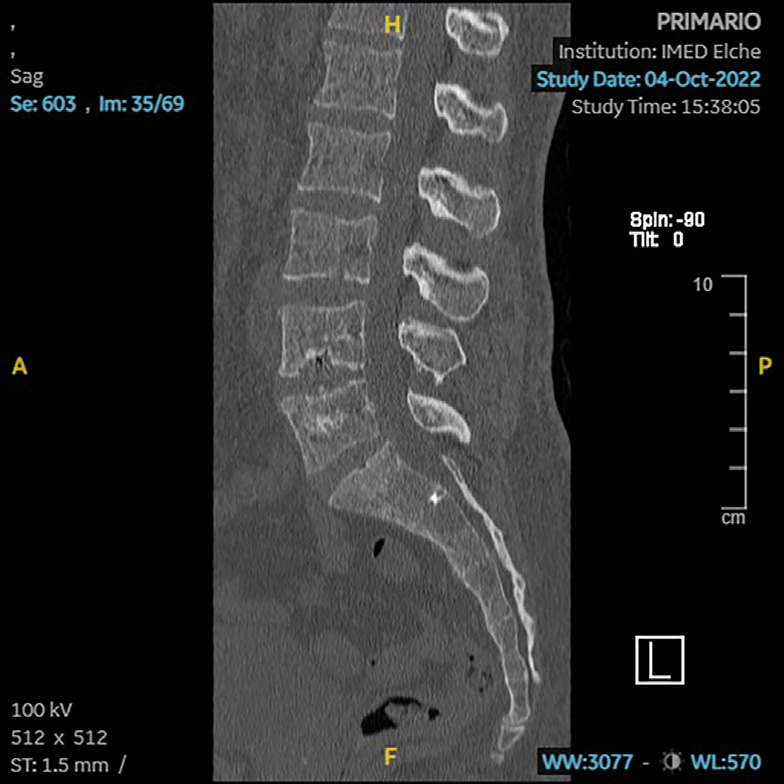

Aporta TC privado (10/2022) donde se aprecia pseudoartrosis L4-5.

RM (09/2023): cambios postquirúrgicos en L4/L5 con signos de sobrecarga mecánica en platillos vertebrales. Estenosis severa de forámenes neurales L4/L5 por hipertrofia de facetas articulares y por patología discal. Patología en el nivel adyacente L3/L4 con discopatía sin hernia y artropatía degenerativa que producen estenosis moderada foraminal bilateral.

En localización extraforaminal derecha L4/L5, engrosamiento focal sólido de la raíz L4 que mide 15 mm de diámetro y que se realza de forma homogénea tras la administración de contraste intravenoso; sugestivo de tumoración de estirpe neural, neurinoma o neurofibroma.

Schwannoma L4 ho.

Pseudoartrosis L4-5.